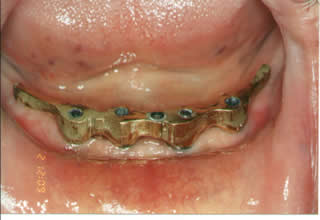

This is a four implants milled-bar supported over-denture. The denture as you can see has an attachment in the middle and two pins at the back that can lock under the implant bar. |